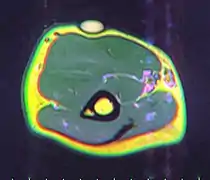

MRI showing lipoma of the arm